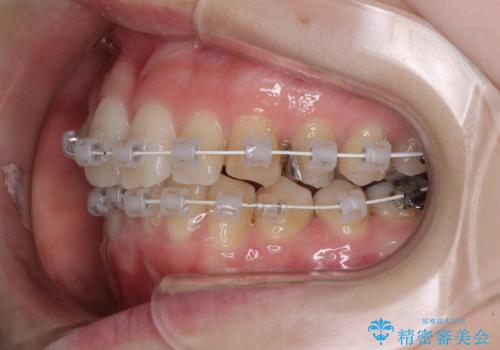

- 矯正装置

- 急速拡大装置・審美装置

- 治療期間

- 1年1ヶ月

急速拡大装置により上顎骨を側方に拡大し、ワイヤー装置により歯列を整えることとしました。